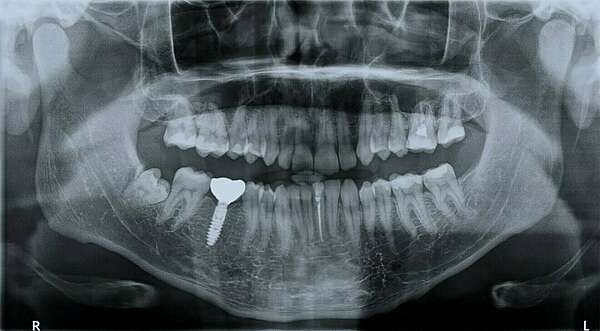

C’est une radiographie panoramique qui consiste en une mise à plat de l’arc dentaire, d’une oreille à l’autre.